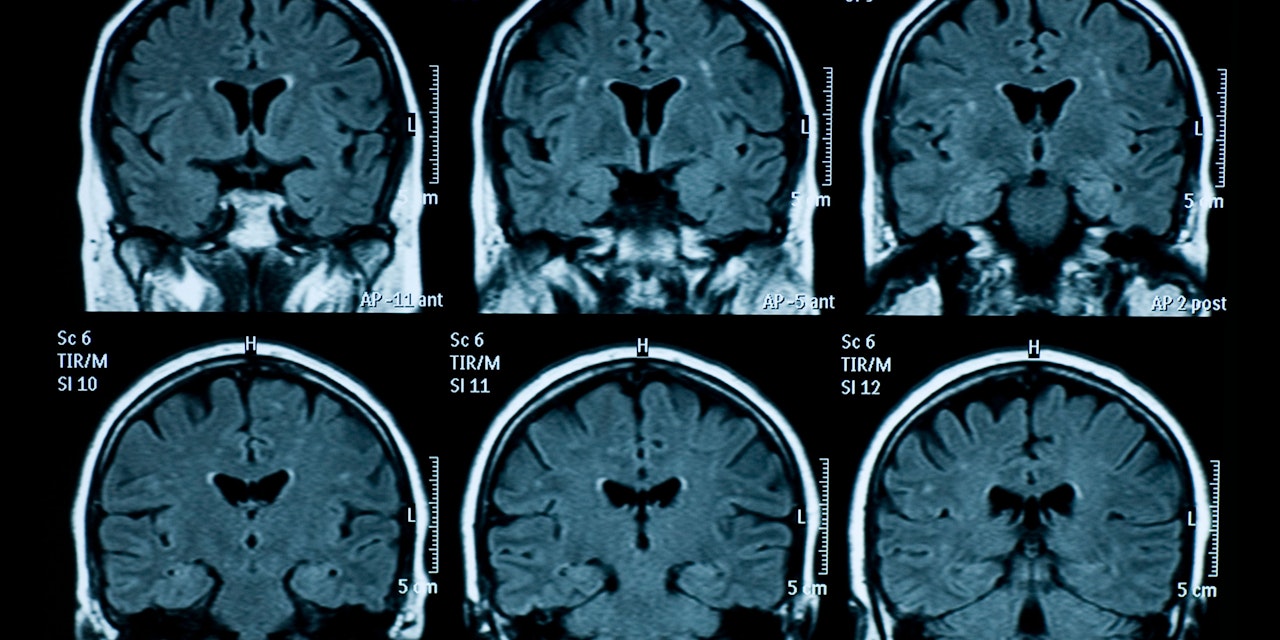

Eine neue Studie aus England zeigt, dass eine Covid-Infektion das Hirn schrumpfen lassen kann. Betroffen sind vor allem die Hirnareale für kognitive Fähigkeiten. Diese Long-Covid-Symptome sind nicht nur bei schweren Verläufen, sondern auch bei "milden" Verläufen möglich, so die Studie. Die Gehirne der Betroffenen wurden zwischen März 2020 und April 2021 untersucht.

So gäbe es bis dato zum Beispiel keine konkreten Hinweise dafür, dass die aktuell dominanten Omikron-Varianten BA.1 und BA.2 oft zu Hirnschäden führen würden. Zudem habe die britische Studie sich hauptsächlich mit der Morphologie, also mit der Form und Struktur des Gehirns, befasst. "Was man auf den Bildern sieht und was effektiv im Hirn abgeht, sind zwei verschiedene Paar Schuhe", sagt Cerny.